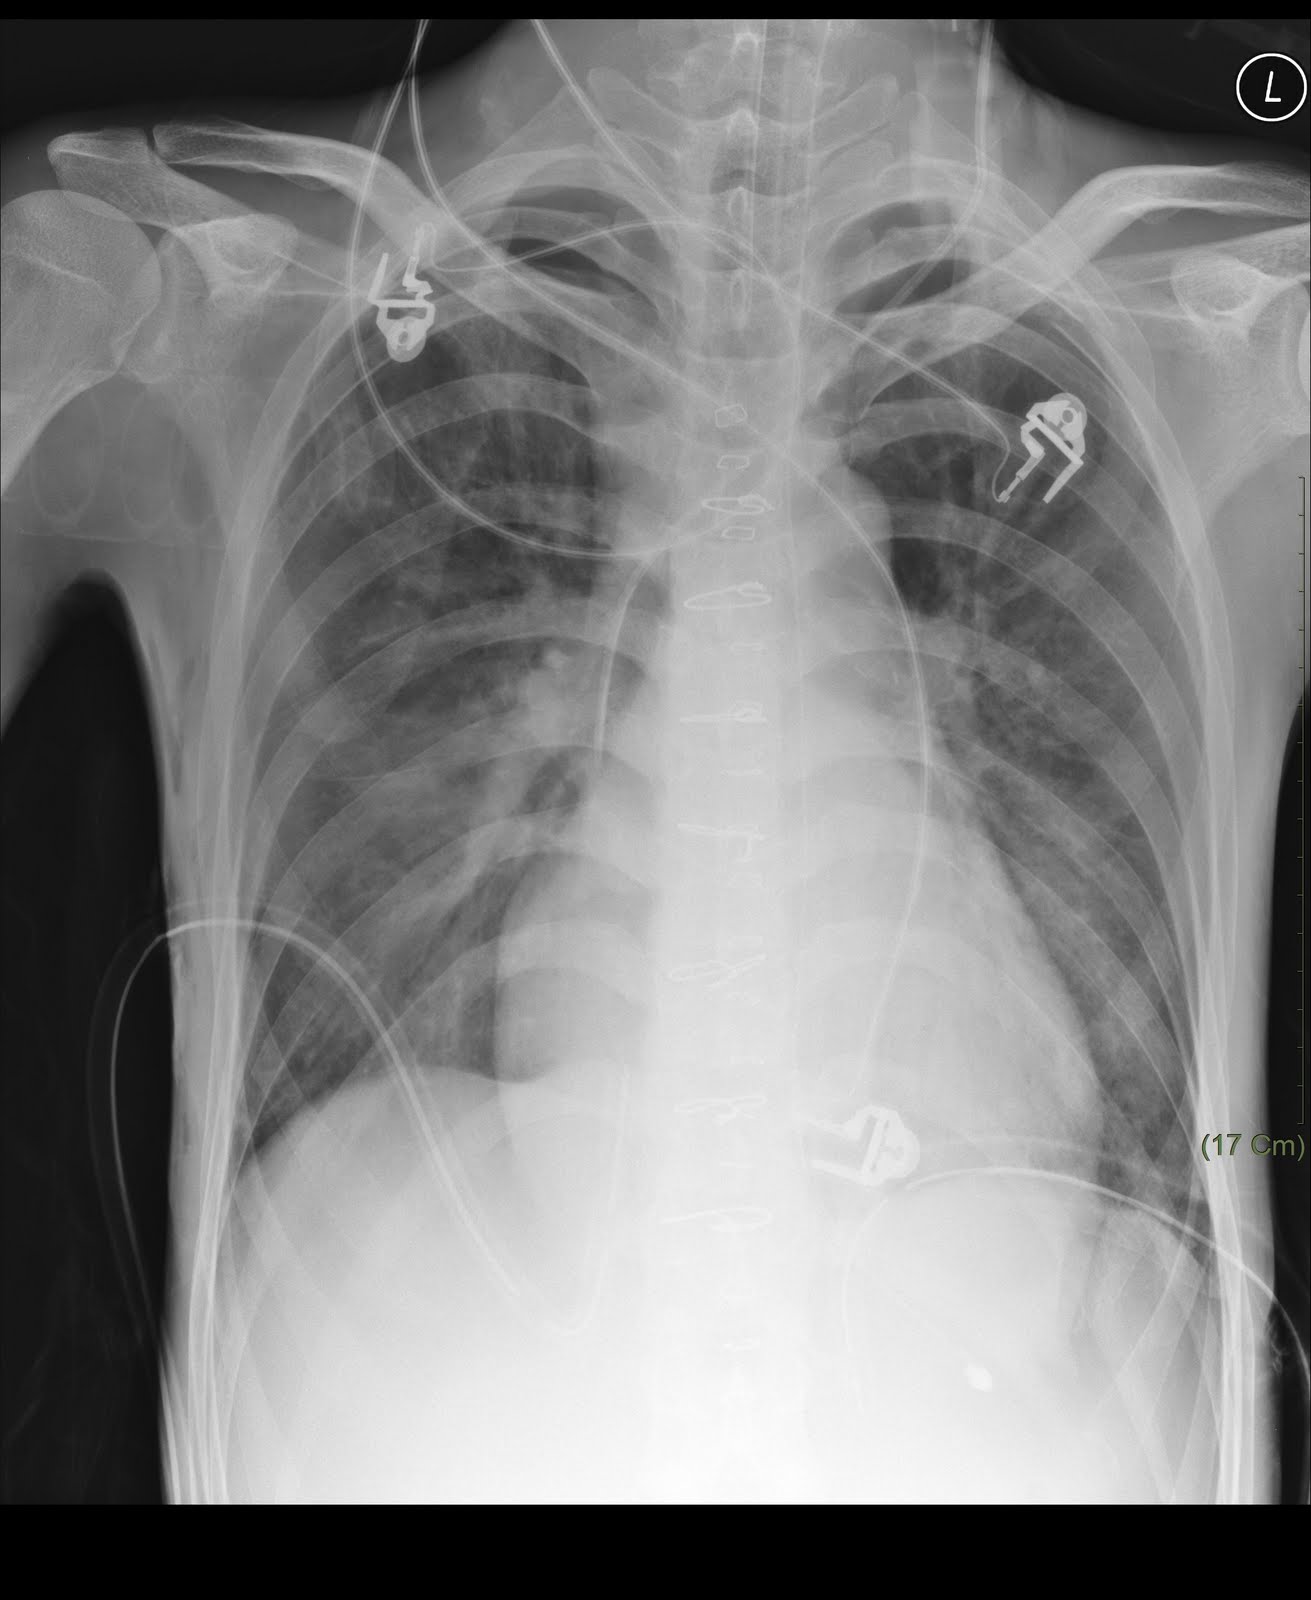

CXR of pneumothorax-1

上圖為右側氣胸(pneumothorax)之CXR,可以明顯的看到在外側2/3肺野(ling field)完全看不到肺紋(lung marking),此CXR中,左側其實也已經放了一根CHEST TUBE了

上圖可以看到右側在放完胸管之後,右肺重新擴張,上一張片子沒有肺紋(黑黑的)的地方已經有肺紋了。